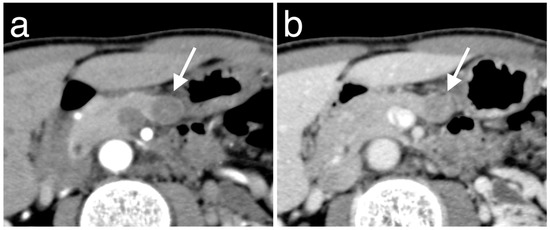

3.3. Enhancement Patterns of Pan-NENs Related to Low or High PAX6 Expression

| Hyperenhancement | 4 | 32 | 0.64 | 0.009 |

| Iso- or hypoenhancement b | 7 (3, 4) | 8 (6, 2) | ||

| Portal phase | ||||

| Hyperenhancement | 3 | 33 | 0.76 | 0.001 |

| Iso- or hypoenhancement b | 8 (6, 2) | 7 (6, 1) | ||